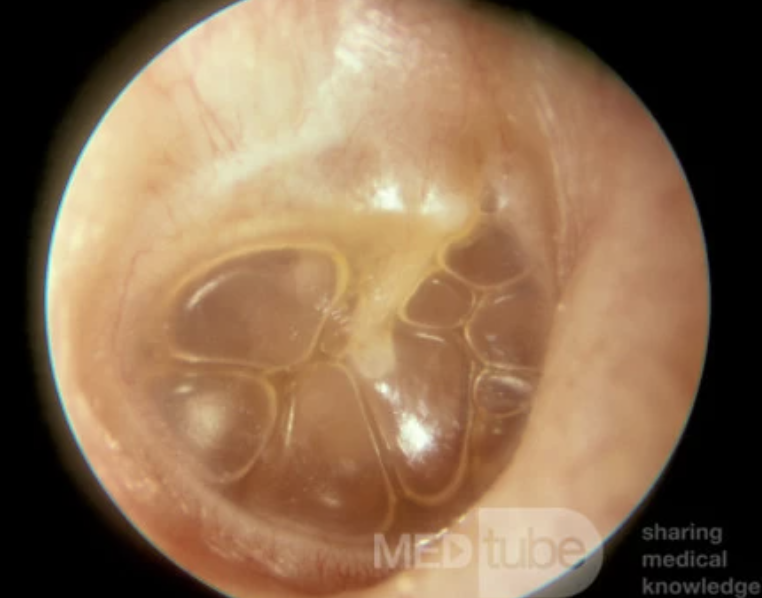

Serous otitis media

Fluid buildup in the middle ear that can follow acute otitis media or caused by obstruction of the Eustachian tube

<p>Fluid buildup in the middle ear that can follow acute otitis media or caused by obstruction of the Eustachian tube</p>